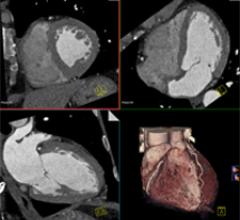

September 27, 2011 — A study in the Sept. 27 issue of the Journal of the American College of Cardiology suggests that early coronary computed tomographic angiography (CCTA) is preferable to rest-stress myocardial perfusion imaging (MPI) when evaluating acute low-risk chest pain in the emergency department.